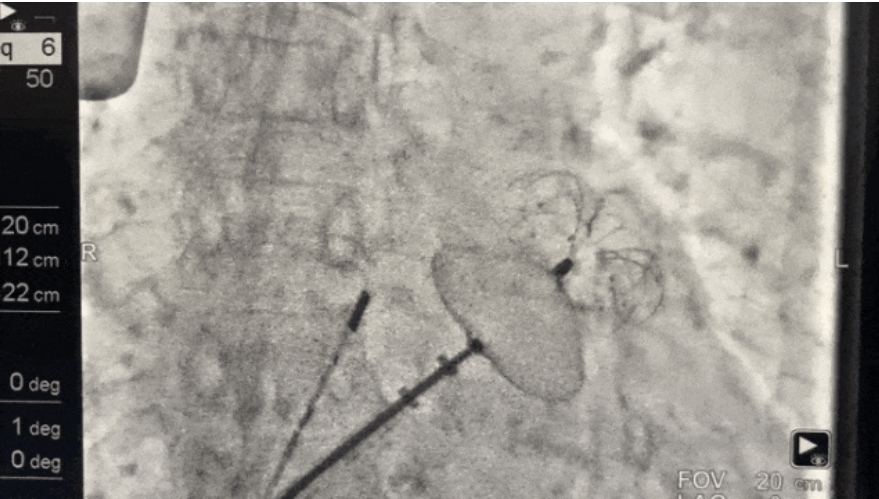

术中,手术团队评估左心耳形态和大小,选择合适大小的封堵器,凭借精确的操作和默契的配合,高效、安全、精准地完成了左心耳封堵。展开后观察位置形态良好,多角度评估显示符合PASS原则,遂释放封堵器。

左心耳封堵器完全释放后,经2次牵拉试验及三轴多普勒扫描确认,封堵器位置稳定,封堵完全,无残余分流,且心影透视未见异常,手术圆满成功,卒中风险得到了精准有效的控制。

▲封堵器展开,左心耳血栓封堵手术成功